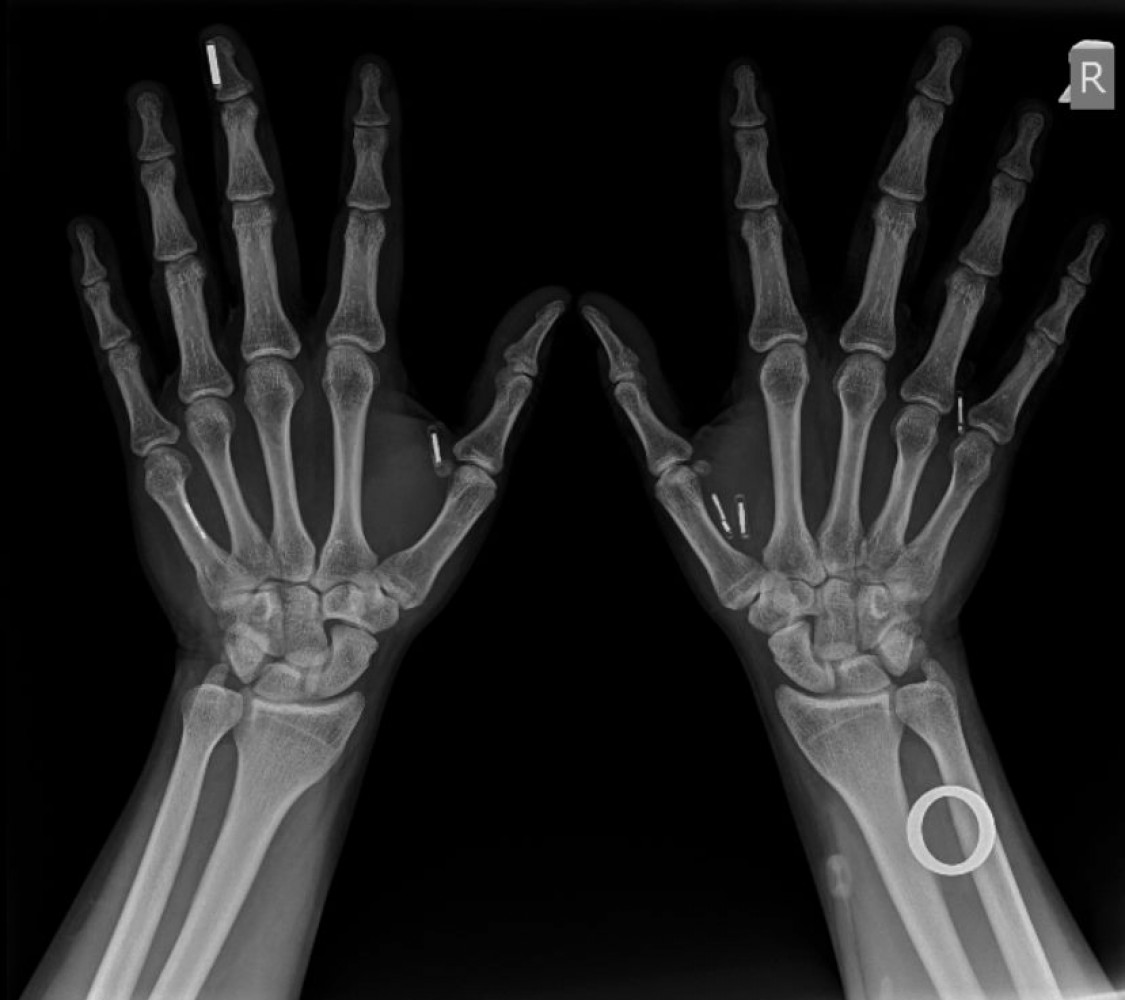

Сама микросхема представляет собой крохотную капсулу, размером с рисовое зернышко, покрытую биостеклом. Микросхема вводится под кожу, как инъекция с помощью шприца и трехмиллиметровой иглы. Сама процедура является практически безболезненной.

Самые большие сложности у Павла возникли при вживлении чипа банковской карты. За неимением другой законной альтернативы в Украине, Павлу пришлось запустить под кожу NFC кольцо. На самом деле оно предназначено для ношения на пальце, но так как сделано из керамики, которая широко используется в стоматологии, может быть использовано как имплант.

«Я себе заказал это кольцо и потом очень долго мучал компанию производителя вопросами, из чего оно сделано, какие сертификаты у него есть, переживет ли кольцо химическую и термическую обработку. Есть три критерия к такому устройству – биосовместимый материал, сохранение функциональности после стерилизации и размер устройства. Два из трех пунктов это кольцо прошло», — продолжает наш собеседник.